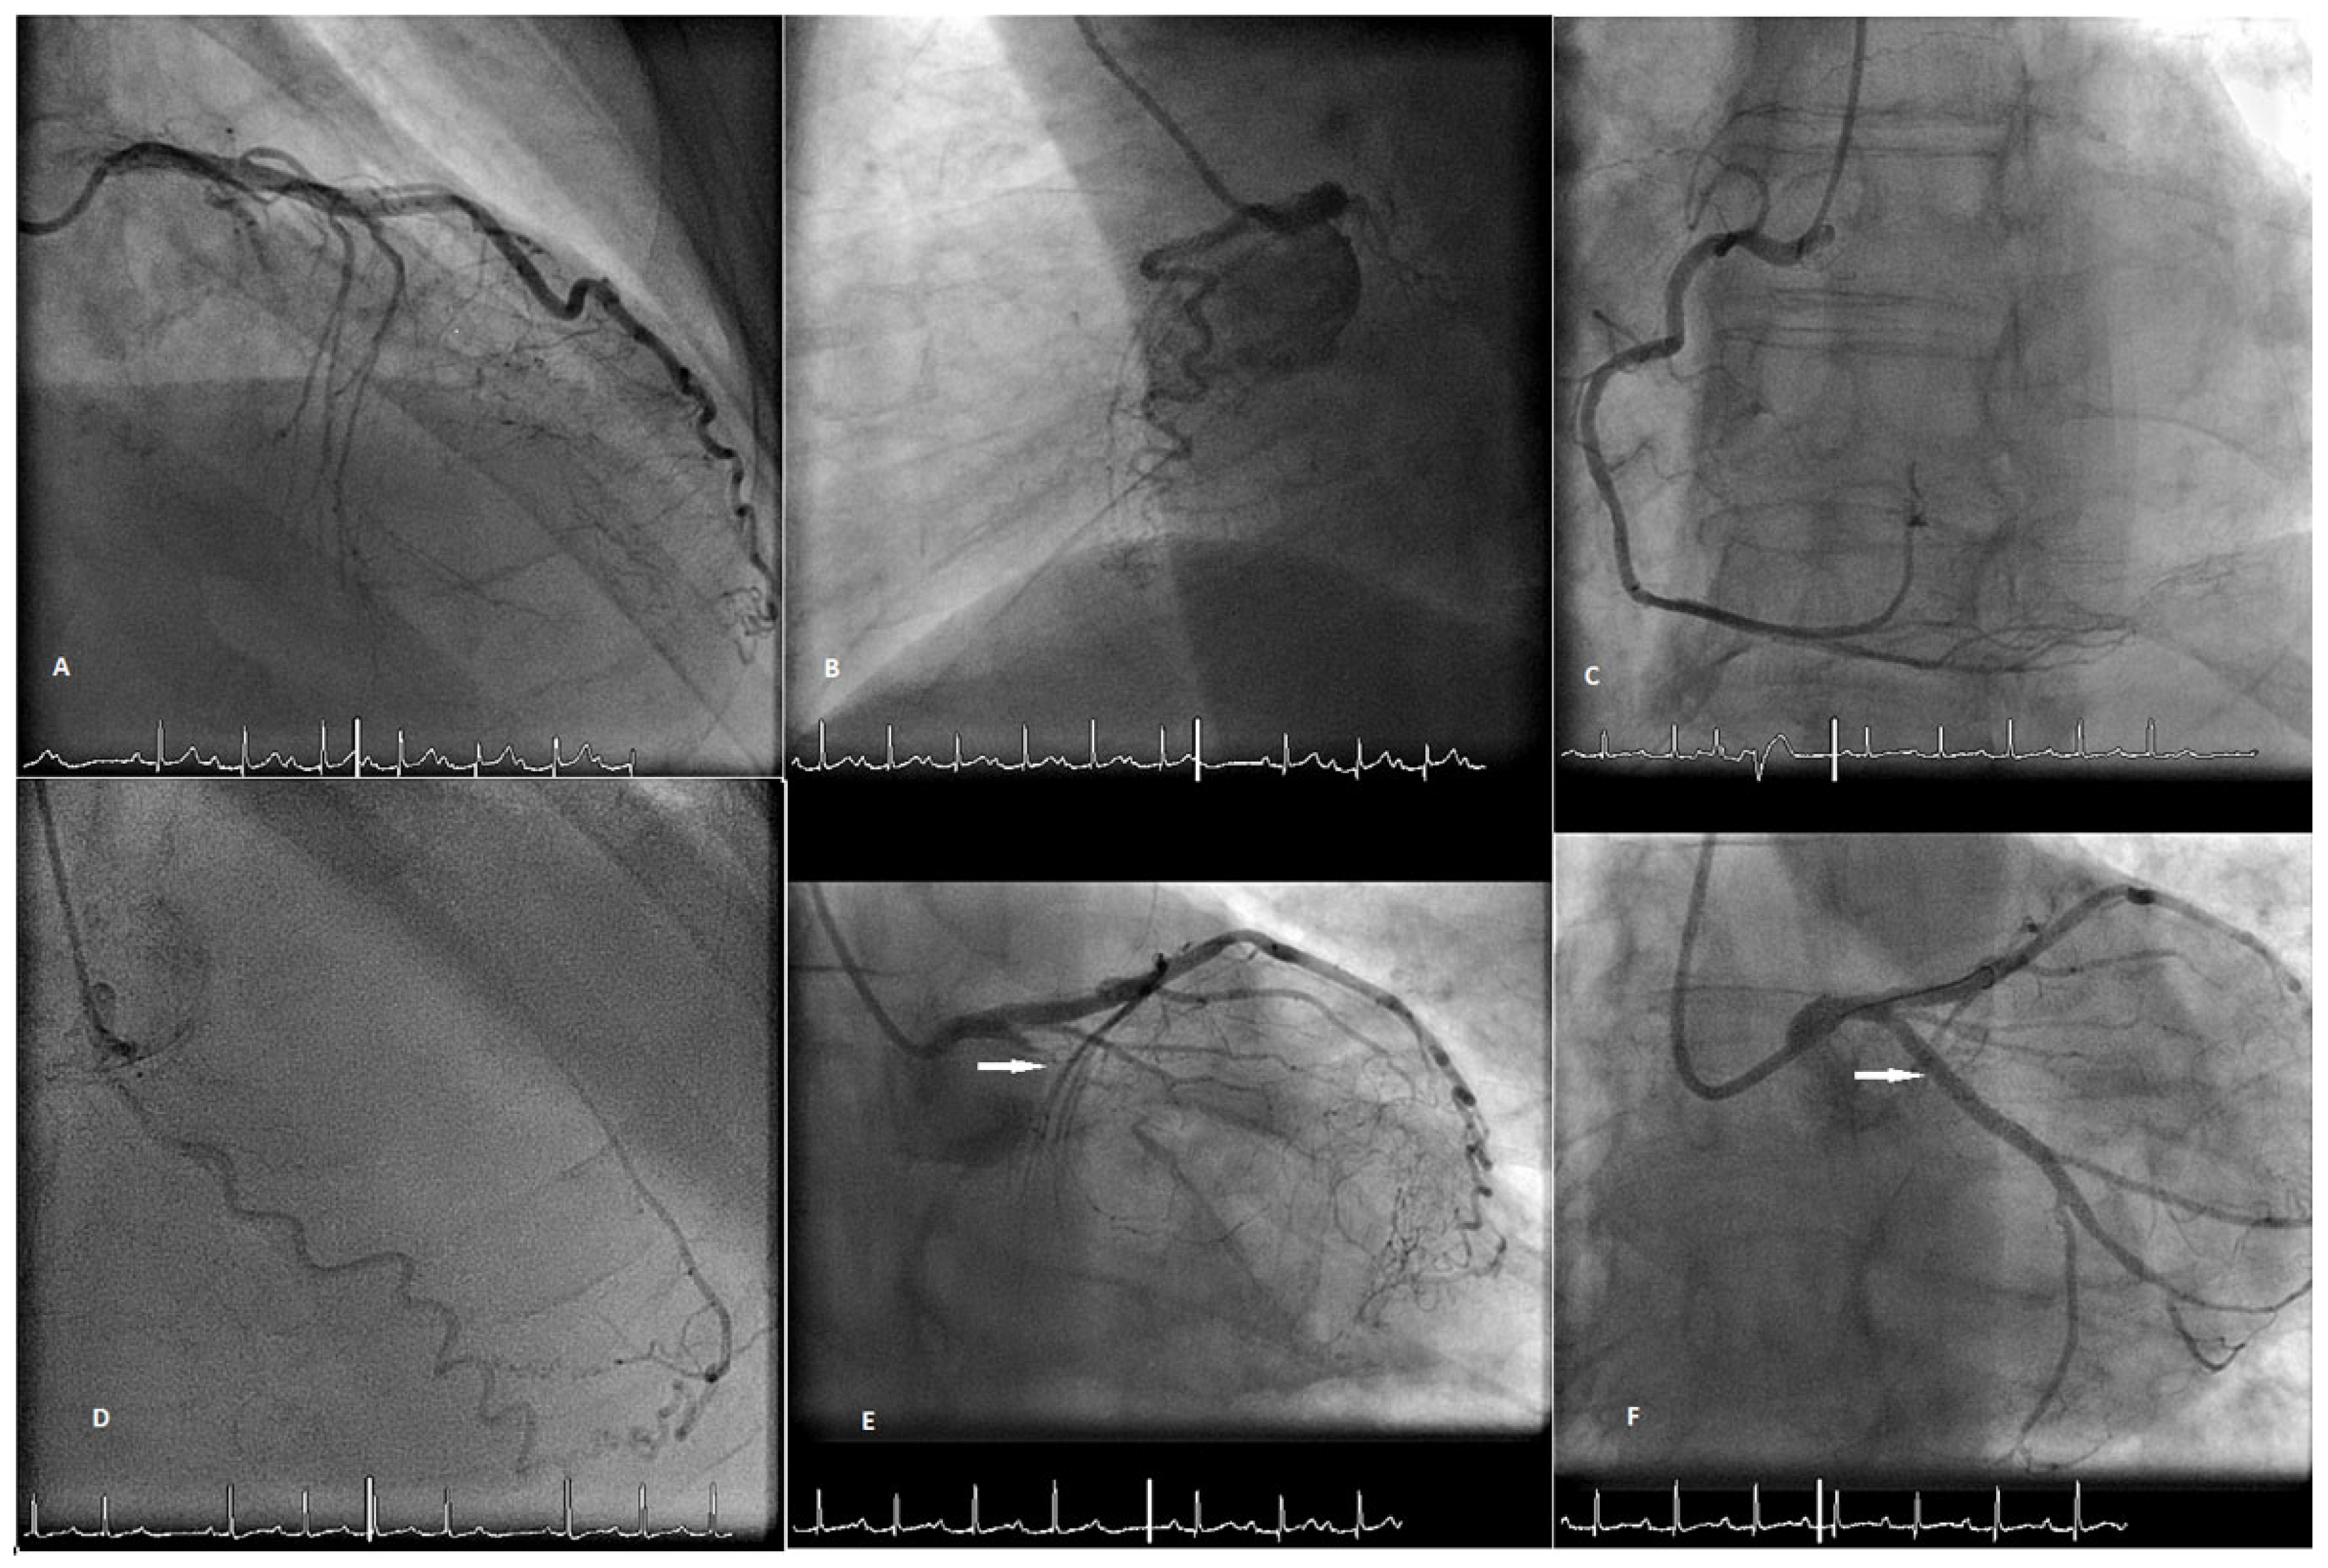

Case Report